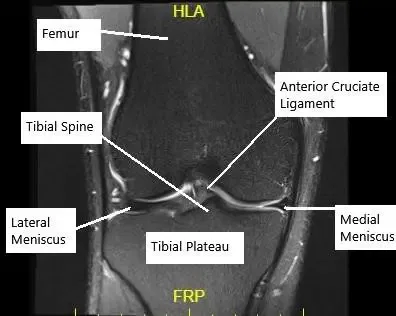

Resonancia magnética de la rodilla en corte coronal que muestra un LCA intacto.

El LCA es uno de los principales ligamentos de la articulación de la rodilla, crucial para la estabilidaddurante actividades como correr, saltar y pivotar. Conecta el hueso del muslo (fémur) con el hueso de la espinilla (tibia) e impide el movimiento excesivo hacia delante de la tibia en relación con el fémur. Sin un LCA que funcione, la rodilla puede sentirse inestable, lo que dificulta la realización de tareas cotidianas y actividades deportivas.

El ligamento cruzado anterior conecta el fémur con la tibia. Su función principal es impedir que la tibia se desplace demasiado hacia delante y controlar la rotación al correr, pivotar o saltar. Sin el ligamento cruzado anterior, la rodilla puede sentirse suelta e inestable.

Para confirmar una rotura del ligamento cruzado anterior y evaluar las estructuras circundantes se utilizan técnicas de imagen como la resonancia magnética. La RM muestra el estado del ligamento y ayuda a planificar el tratamiento.